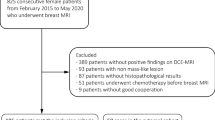

A dataset of 402 malignant and 257 benign lesions was identified. Two radiologists assigned the KS. If a lesion with KS > 4 had ADC > 1.4 × 10−3 mm2/s, the KS was reduced by 4 to become KS+. In order to consider the full spectrum of ADC as a continuous variable, the KS and ADC values were used to train diagnostic models using 5 ML algorithms. The performance was evaluated using the ROC analysis, compared by the DeLong test. The sensitivity, specificity, and accuracy achieved using the threshold of KS > 4, KS+ > 4, and ADC ≤ 1.4 × 10−3 mm2/s were obtained and compared by the McNemar test.